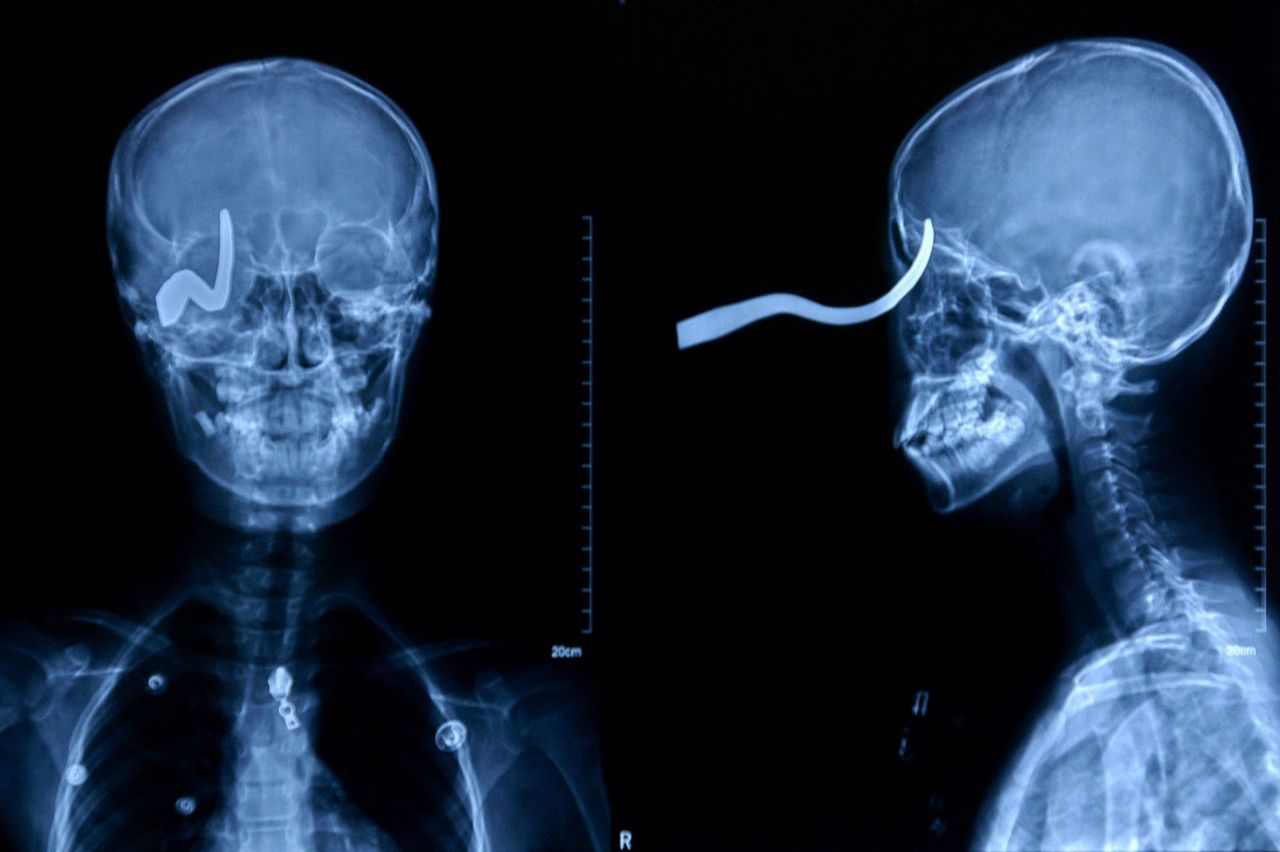

メタリカのスタンド攻撃うけてるやん

メタリカもそうだが、何らかのスタンド攻撃を疑うのも解らんでもないww

21はその後矢を引き抜いて飛び出た目玉を食べそう。

メタリカァ!

どこの世界に「弓」を飛ばして人に刺すバカがいるんだろうw

弓から矢を発射するんだろうがw